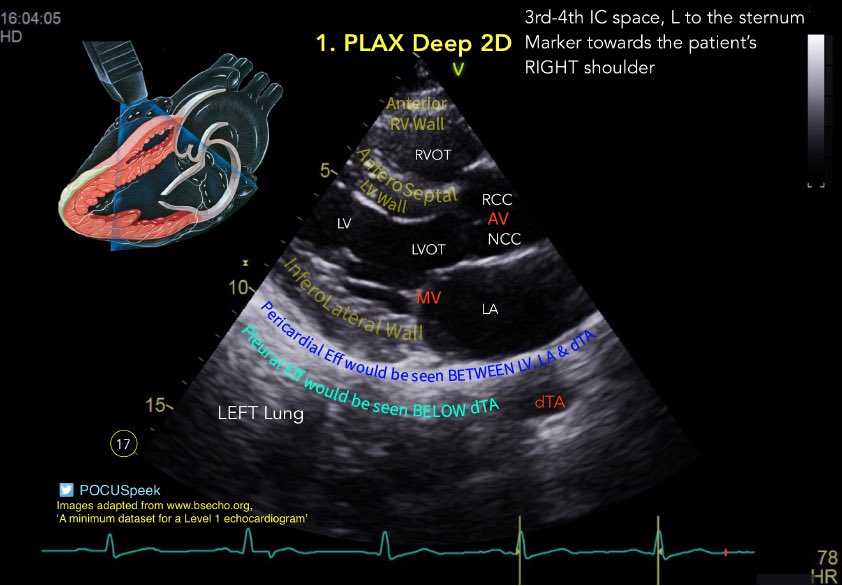

Annotated PLAX views #firstecho #POCUS for @BSEcho level 1 or #FUSICheart @pocusfoamed 🧵 PLAX Deep 2D 👇

🧵 PLAX Deep 2D 👇